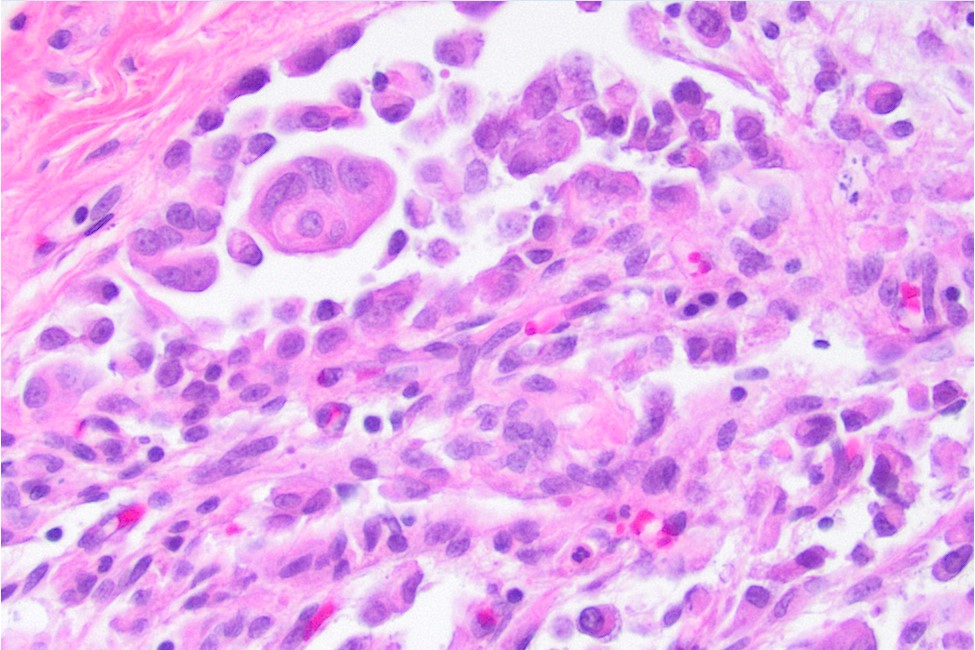

Histological examination of the patient’s pericardial biops­y specimen revealed infiltration by discohesive pleomorphic rhabdoid cells with prominent pink intracytoplasmic inclusions (figures 2-4), vesicular nuclei with prominent nucleoli, and frequent mitotic figures, including atypical forms. The tumor was positive for the cytokeratin cocktail, EMA, and vimentin. Muscle markers (myogenin and myo-D1), S100, and CD30 were negative (figure 5). There was also a loss of INI-1 immunostaining (figure 6). The findings on cytologic evaluation of the patient’s pericardial fluid were congruent with the histologic findings.